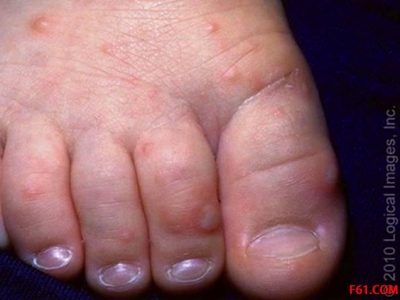

脚底

小红疙瘩

手足口病脚底长了很多小红疙瘩图

手足口病表现为足部前掌处出现数量较多的红色丘疹、疱疹,形似小红疙瘩,但并不明显突出于皮肤表面,用手触摸可有坚实感。疱疹内液体较少,可有轻度混浊,周围有明显的红晕。建议减少走动和摩擦,以避免皮损处破溃。

小红疙瘩 · 丘疹

手足口病脚底长了好多小红疹子图

手足口病早期阶段,在脚底部位出现密集的红色丘疹,多为针尖大小,触摸时有明显的凸起感,而后逐渐发展至米粒大,形成小疙瘩,皮损周围存在淡淡的红晕,此时避免摩擦或烫洗局部,以免产生不适感。

脚趾

水疱

手足口病大脚趾上起水疱图

手足口病患者的大脚趾出现米粒至豆粒大小的水疱,呈椭圆形,比较规则,水疱中含有一点清亮液体,并且周围伴有红晕,按压可导致红晕消失。